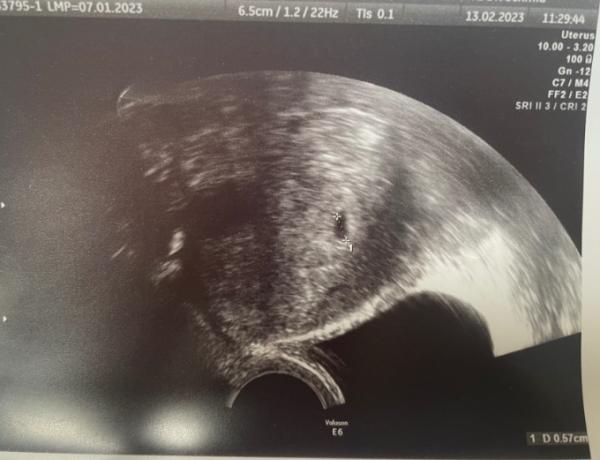

Hallo Ich bin in der Frühschwangerschaft bei 6+4. ich war letzte Woche beim FA und beim Ultraschall konnte man eine Fruchthöhle sehen. Das war bei 5+2 oder so, bin mir nicht ganz sicher. Meine FA war so enthusiastisch und ich traue mich gar nicht, mich auf irgendwas zu freuen. Ich hatte im November erst eine EUG mit Notoperation, geplatztem EL etc. Konnte zwar erhalten bleiben, aber irgendwie … das war meine erste Schwangerschaft und wir hatten uns schon gefreut. Jetzt traue ich mich nicht, mich auf irgendwas zu freuen. Ich bin mir irgendwie sicher, dass irgendwas schief gehen wird. Mir war jetzt zwar immer wieder übel, es geht aber weg, sobald ich esse. Es ist auch nie sonderlich schlimm, übergeben musste ich mich nie. Manchmal hab ich auch bedenken, dass ich mir die Übelkeit nur einbilde. Meine Brüste schmerzen etwas, aber aushaltbar. Ein bisschen, wie bevor ich meine Tage bekomme. Also alles in allem… ich fühle mich glaub einfach „zu wenig schwanger“ ohne wirklich zu wissen, wie man sich dabei fühlen müsste. Mein nächster Termin beim FA ist erst in 2 Wochen… habt ihr mir vielleicht irgendwelche Ratschläge oder Tipps? Ich bin kurz vorm verrückt werden.

Bild zu Unsicherheiten und Angst - Schwanger - wer noch? Rund um die Schwangerschaft